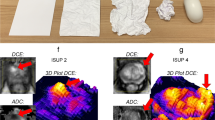

Our initial discovery cohort consisted of 10 patients, in which diameter measurements on gross pathology were available as reference standard. Both mpMRI and FD size estimates correlated well with gross pathology measurements (mpMRI: R2 = 0.96; FD: R2 = 0.92) and did not show significant diameter differences (mpMRI: Δdiameter = 0.9 mm, p = 0.32; FD: Δdiameter = −0.6 mm, p = 1.0). Moreover, measurements on FD maps correlated excellently to mpMRI (R2 = 0.88) without significant differences between those methods (p = 0.63). In contrast, CT measurements systematically underestimated tumour diameter in comparison to gross pathology (Δdiameter = 5.7 mm, p = 0.03). A representative example with correlation to gross pathology is depicted in Figure 1 alongside a boxplot to summarise diameter differences measured on each modality to pathological reference. Detailed statistics for the discovery cohort are summarised in Table 2.

Representative example of pancreatic ductal adenocarcinoma in the pancreas head with gross pathology from the resected specimen as reference. CT with fractal dimension (FD) map of perfusion (left and middle columns with yellow frames, FD colour-code given in the bottom inset) and MRI as reference. A contrast-enhanced, fat-saturated T1 GRE image (acquired after administration of a gadolinium-based contrast agent) in the arterial phase (Gd+) is shown to illustrate tumour conspicuity alongside a diffusion-weighted image with b-value = 800 s/mm2 (DWI - b800), which was used for size estimation. The panels with yellow and green frames are magnifications of the tumour area in CT and MRI, respectively, and correspond to the marked areas in the images with original resolution. Gross pathology depicts a cross-section through the pancreas head and the tumour, which measured 25 mm in maximum diameter. Tumour diameter on CT was 15 mm, on FD map 26 mm, and on MRI 24 mm. The boxplot on the right summarises differences in diameter measurements between gross pathology as reference and each imaging estimation method. CT significantly underestimated tumour diameter with a mean difference of −5.5 mm (confidence interval: −9.5 to −1.5), whereas MRI and FD measurements did not significantly differ from gross pathology. *p = 0.03; C, tumour core; R, tumour rim; NP, non-tumourous pancreatic tissue; D, duodenum; Ao, aorta